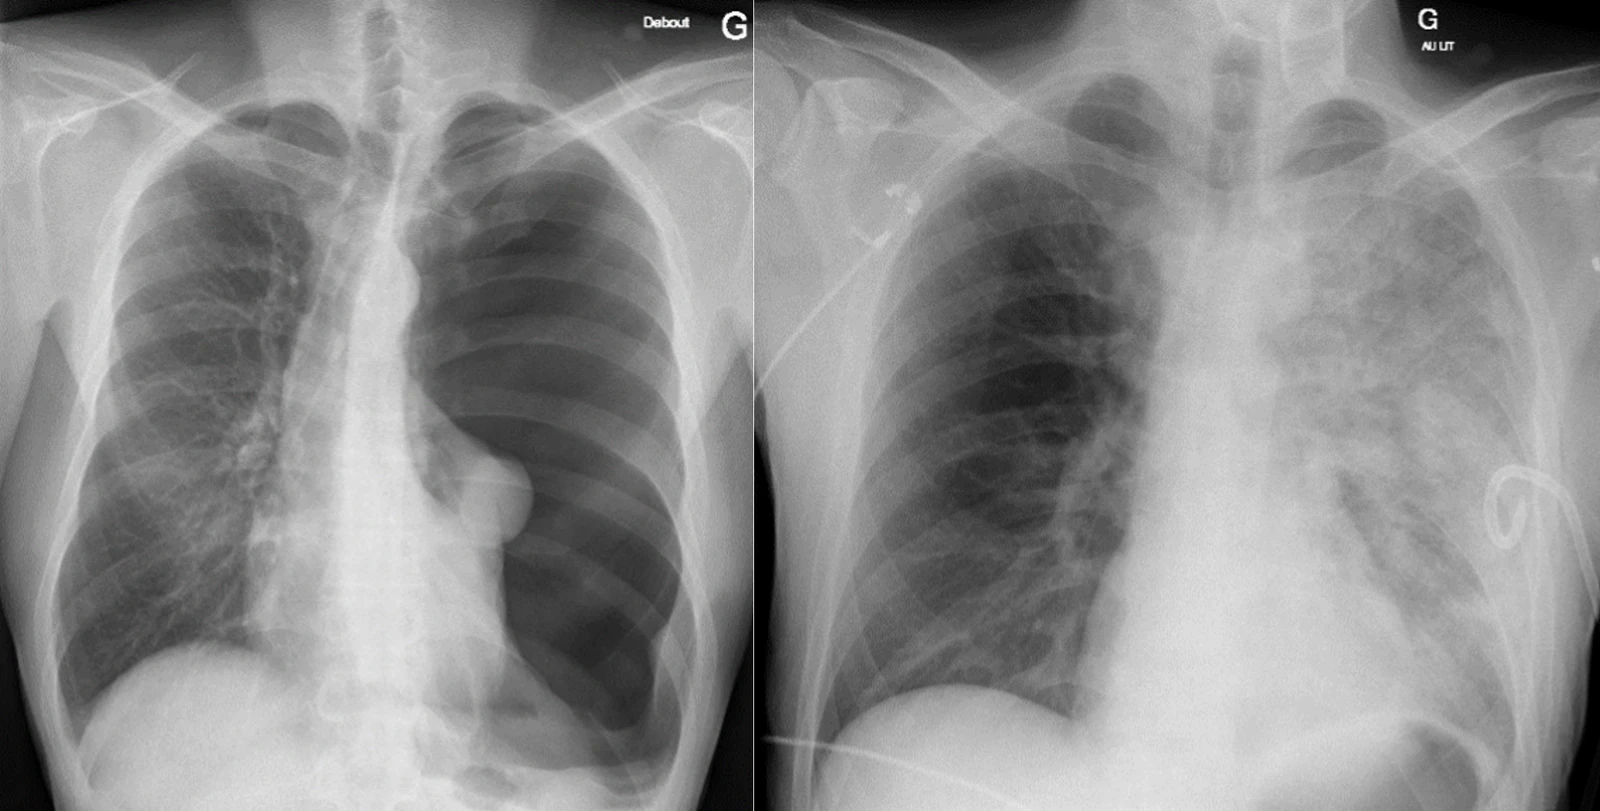

1. À gauche : pneumothorax

2. À droite : œdème de réexpansion

L’image de gauche est une radiographie pulmonaire réalisée debout en antéro-postérieure, d’un patient jeune se présentant pour une dyspnée et une douleur thoracique. Elle révèle un pneumothorax massif avec une légère déviation du médiastin vers la droite. Un pigtail est mis en place dans le 5ème espace intercostal gauche. Le patient est hospitalisé. Dans les 12 heures qui suivent, le patient développe une dyspnée et tachypnée avec une désaturation à 84% à l’air ambiant. La radiographie de gauche montre un œdème de réexpansion de toute la plage pulmonaire gauche.